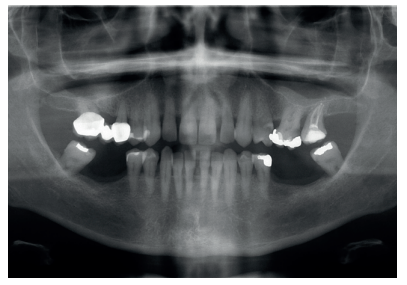

Caso clínico: Se presenta el caso clínico de una paciente con hipertensión, diabetes tipo II, hipotiroidismo, depresión, obesidad y déficit de vitamina D. Se hace una revisión de la actuación del odontólogo en la clínica cuando se presentan pacientes con dichos cuadros y las consideraciones a tener en cuenta con respecto a la prescripción y administración de medicación. El objetivo es presentar recomendaciones de tratamiento a partir de un caso clínico de una paciente con varias afecciones sistémicas en la que se realiza un tratamiento multidisciplinar. Para eso se ha realizado una revisión narrativa que se considera útil para la actividad clínica diaria

Clinical case: The clinical case of a patient with hypertension, type II diabetes, hypothyroidism, depression, obesity and vit D deficiency is presented. A review is made of the performance of the dentist in the clinic when patients with these conditions appear and the considerations to take into account with respect to the prescription and administration of medication. The objective is to present treatment recommendations based on a clinical case of a patient with several systemic conditions in which a multidisciplinary treatment is carried out. For this, a narrative review has been carried out that is considered useful for daily clinical activity.